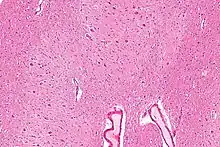

Micrograph of the dentate nucleus (pale pink). H&E stain.

The architecture of cerebellum has a form that resembles the structure of a crystal, so a slice anywhere in the cerebellum gives repeated architecture. The eight cerebellar nuclei, located within the deep white matter of each cerebellar hemisphere, are grouped into pairs, with one of each pair in each of the two hemispheres. As a chunk of tissue, the dentate nucleus with overlying cerebellar cortex makes up a functional unit called the cerebrocerebellum. Thus, there is a part of cerebellum that communicates exclusively with the dentate nucleus.[4]